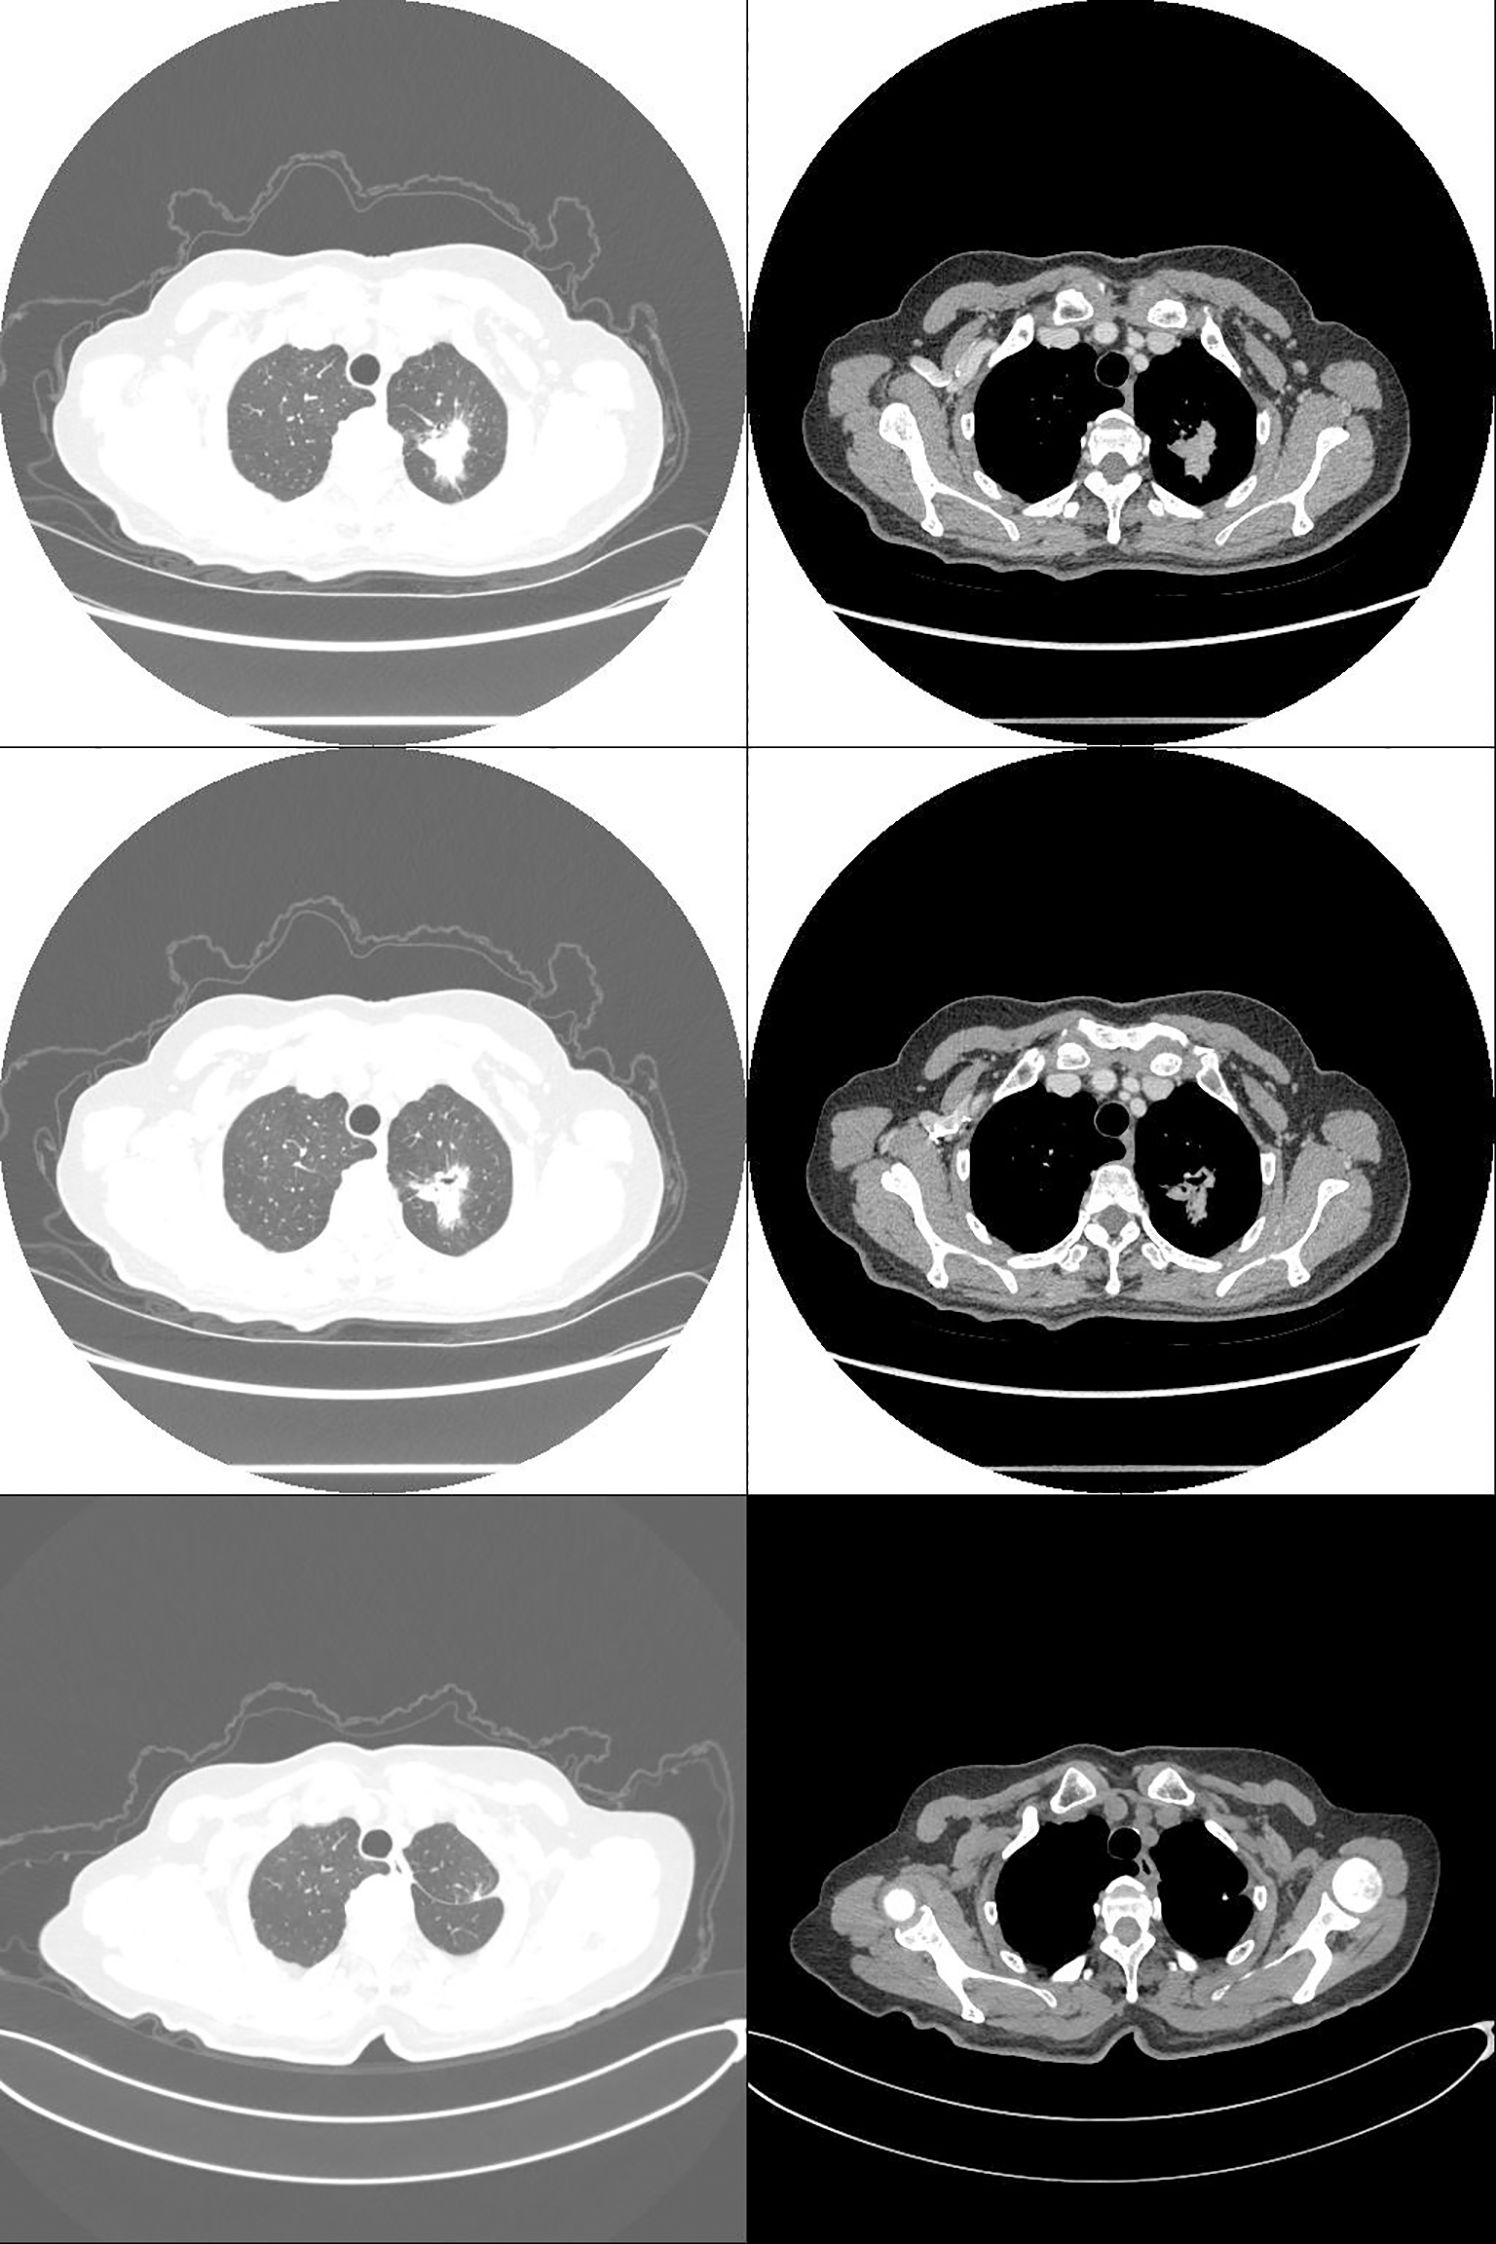

A 75-year-old female patient presented with a one-week history of cough and productive sputum with intermittent hemoptysis. Chest computed tomography (CT) demonstrated a patchy soft tissue density mass in the apicoposterior segment of the left upper lobe, measuring approximately 30.1×22.9 mm (Figure 1). The lesion exhibited ill-defined margins, spiculation, and partial ground-glass opacity, without evidence of lymphadenopathy or distant metastasis. The patient had no history of smoking, chronic inflammatory disease, autoimmune disorders, or bleeding diathesis.

Three weeks after surgery, follow-up laboratory testing showed a reduction in platelet count to 572 × 109/L (Figure 2). Chest CT demonstrated interval shrinkage of the left upper lobe consolidation (Figure 1), and tumor markers normalized (CEA: 3.31 ng/mL; NSE: 12.40 ng/mL). The patient received hydroxyurea and enteric-coated aspirin for six months postoperatively, after which treatment was discontinued as the platelet count progressively declined and stabilized. No adjuvant chemotherapy or targeted therapy was administered. The patient has since remained under surveillance with no evidence of tumor recurrence.

Figure 1. Computed tomography: non-small cell lung cancer (NSCLC) in the left upper lobe (pT2aN0M0, stage IB; 30.1 × 22.9 mm). Preoperative (top two rows) and postoperative (bottom row) images.